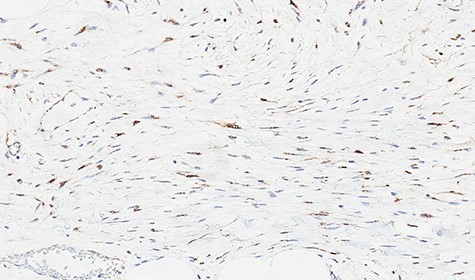

Microscopically, the lesion presented as proliferation of spindle cells without atypia, a low mitotic index and a fibrous stroma rich in collagen (Figs 4 and 5). IHC specimen showed positive nuclear immunoexpression for beta-catenin and focal immunoexpression for smooth muscle actin (Fig. 6). The immunoexpressions for cytokeratins, desmin, caldesmon, protein S CD117, DOG1, CD34, STAT6 and S100 were all negative.

Immunohistochemical study showing positive nuclear expression for beta-catenin.